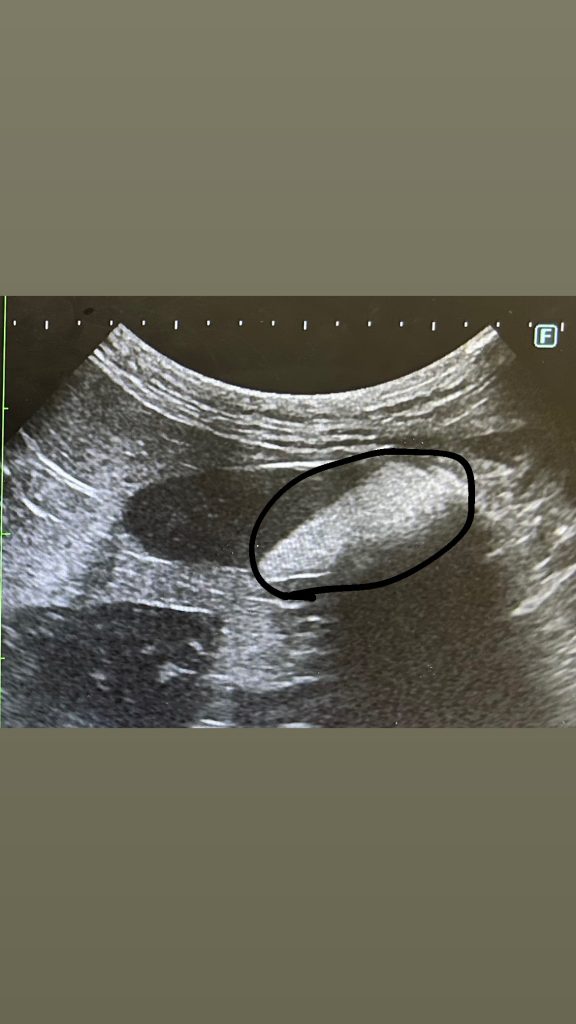

これが1ヶ月前のじみの膀胱ね。黒で囲ってる中の白いのが砂💦

これが膀胱の中で動いて動いて石になるらしい。砂の時点で運動やらお水いっぱい飲ませておしっこで出すのがベストなのよね。